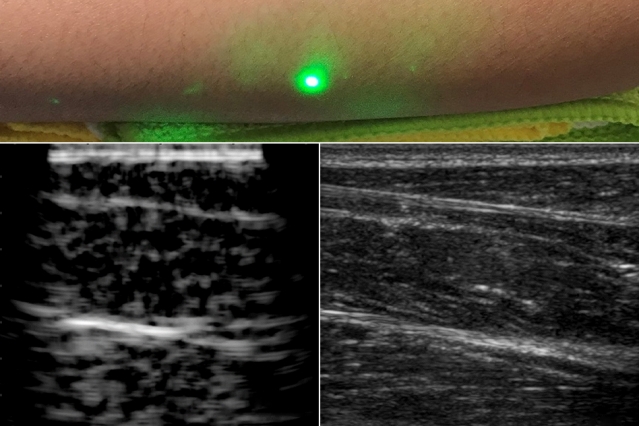

В статье, опубликованной в журнале Light: Science and Applications, команда МТИ отмечает, что они сканировали предплечья нескольких добровольцев и наблюдали общие черты тканей, такие как мышцы, жир и кости, вплоть до 6 сантиметров под кожей. Эти изображения, которые они сравнивали с данными обычного УЗИ (см. рис.), были получены с помощью лазеров, сфокусированных на добровольце с расстояния в полметра.

Инженеры МТИ придумали альтернативный метод, который не требует контакта с телом, чтобы "заглянуть" внутрь пациента. Новая методика лазерного ультразвука использует безопасную для глаз и кожи лазерную систему для удаленного получения изображения внутри тела человека. При испытаниях на коже пациента один лазер дистанционно генерирует звуковые волны, которые отражаются от тела. Второй лазер, также находящийся на расстоянии, обнаруживает отраженные волны, которые исследователи затем переводят в изображение, похожее на обычное ультразвуковое исследование.